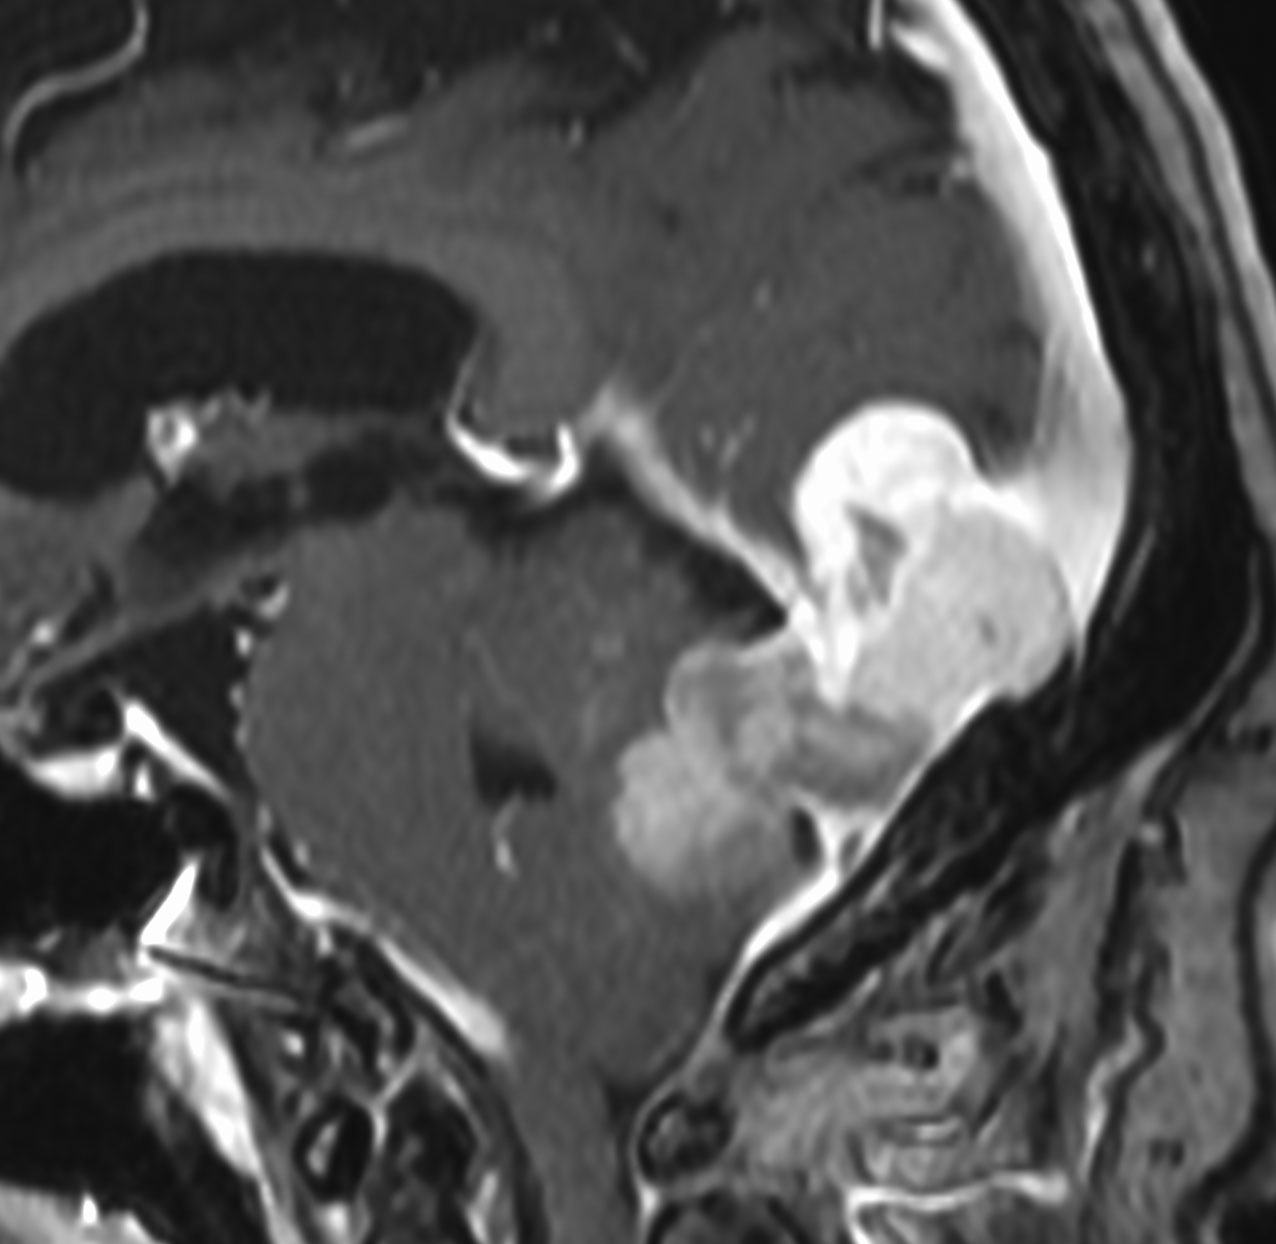

1984年 19歳の時に,松果体のジャーミノーマに全脳照射45グレイで治療されました(左CT)。1997年左蝶形骨縁にヘマンジオペリサイトーマが発生しました(中央と右のMRI)。手術で全摘出しましたが4年後,2001年に脊髄に播種再発してつらい経過を辿りました。眼窩壁を破る典型的なヘマンジオペリサイトーマの像で,放射線誘発髄膜腫との鑑別がとても大切なものです。